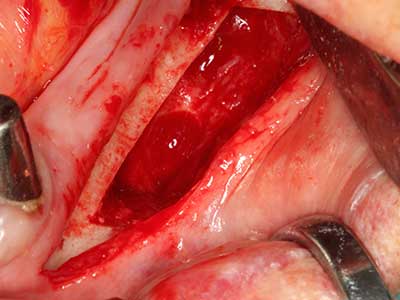

La piezochirurgia presenta altri vantaggi per quanto riguarda la raccolta di blocchi ossei. Oltre all'elevata precisione dell'osteotomia appena descritta, l'utilizzo di puntine per sega molto sottili permette di minimizzare in maniera significativa la perdita di materiale. È molto probabile che si verifichi una maggiore perdita di materiale durante la raccolta utilizzando puntine di strumenti più spessi, in particolare delle frese Lindemann (Lakshmiganthan, Gokulanathan et al. 2012). La separazione basale, necessaria in particolare per i trapianti di blocchi nella zona retromolare, viene semplificata grazie a seghe specificatamente progettate di forma rettangolare; di conseguenza la piezochirurgia è considerata una procedura precisa, semplice e sicura per la raccolta di blocchi di osso nella zona retromolare (Happe 2007) (figg. 1-12).